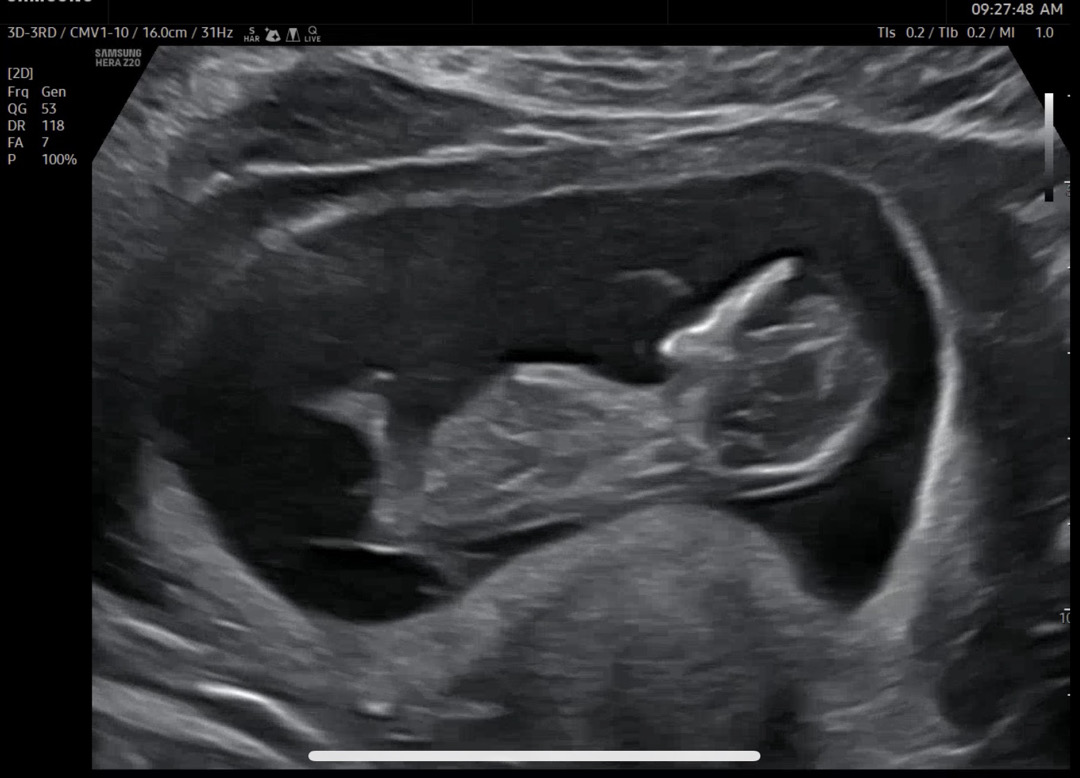

각도법 고수님들 부탁드립니다

아들일까요 딸일까요 너무너뮤노무 궁금해요~~~! 각도법 고수님들 알려주시면 감사하겠습니다💖